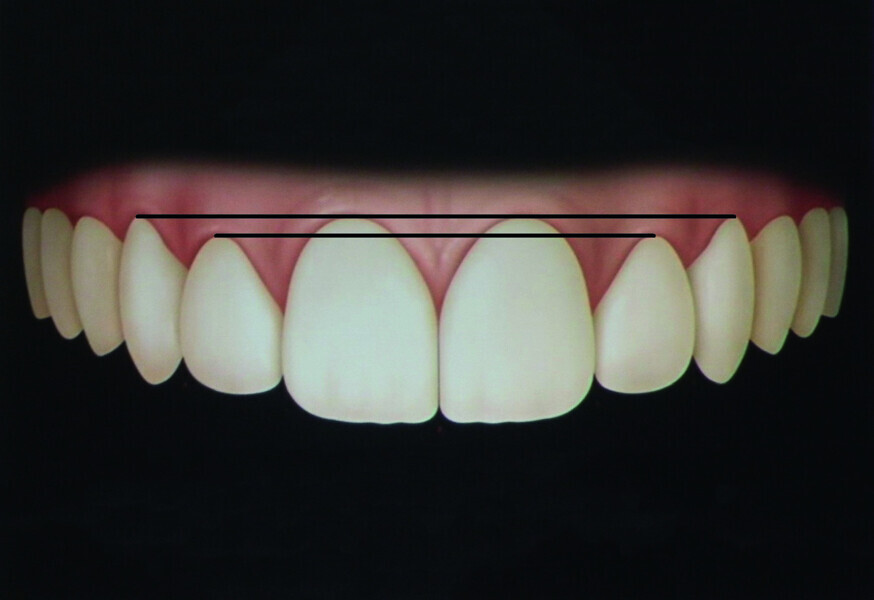

Orthodontic management of maxillary lateral incisors agenesis